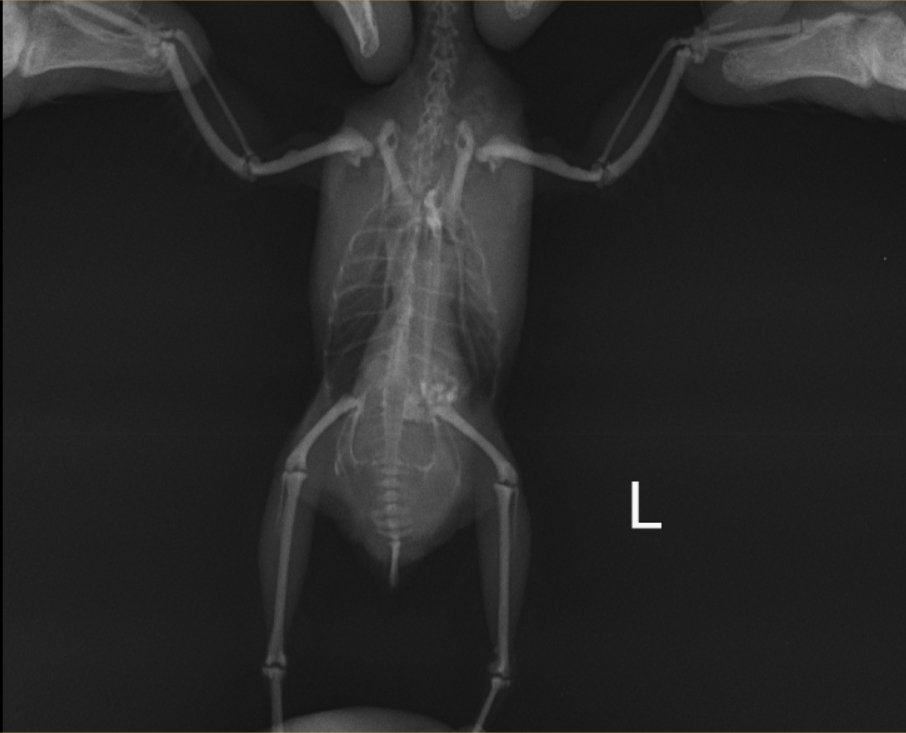

Волнистый попугай Самка, 3 года Зерносмесь Престиж (Бельгия), сенегальское просо РИО, минкамень, сепия, минеральная смесь РИО, фрукты-овощи, каша вареная (гречка+рис не шлифованный+геркулес), Vinka+кальций 2 раза в год при линьке Клетка ферпласт, в большой светлой комнате около стены, на уровне глаз, световой день лето 14 часов, зима 11 часов (режим соблюдается постоянно) 20.05.18 обнаружена шишка внизу и немного слева на животе. Выросла за 1 день буквально. Помет укрупнился и стал реже, птица тужится при этом. Стала быстро утомляться, после полетов появилась отдышка. Хвост немного опущен и двигается в такт дыханию. Аппетит есть. До этого я заметила, что восковица перестала коричневеть уже около года не меняла цвет, но не придала этому значения, птица живет без самца. 24.05.18 попали на прием в Кобру, сделали рентген. Мнение доктора-это липома, но, возможно, есть и злокачественное образование, т.к. на снимке видны затемнения. Прописала 2 капли в день (утро и вечер) суспензию Локсиком для начала, далее идем на повторный прием в субботу 26.05.18. Локсиком принимаем, визуально по птице реакции на препарат не вижу (отдышка после полетов не ушла, когда отдыхает дышит тяжело периодически). Посмотрите, пожалуйста, рентгены со своей стороны, Ваше мнение - видны злокачественные образования или нет? Какую порекомендуете схему лечения?